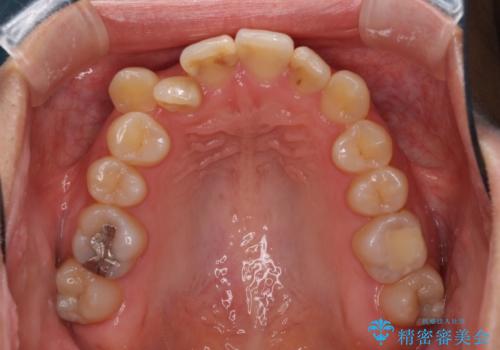

- 上下の八重歯を気にして来院された患者様です。

八重歯の後ろの歯を1歯抜歯し、補助装置(リンガルアーチ)を用いて八重歯の位置を改善し、その後インビザラインにより矯正治療を行うこととしました。

右側のみ上下小臼歯を抜歯したため、上下の正中が右にずれてしまう可能性があります。

また、元々右側は上下が咬み合っていないため、矯正をしても咬み合わないことも考えられました。

治療期間はかかりましたが、正中も合い、綺麗な仕上がりとなりました。